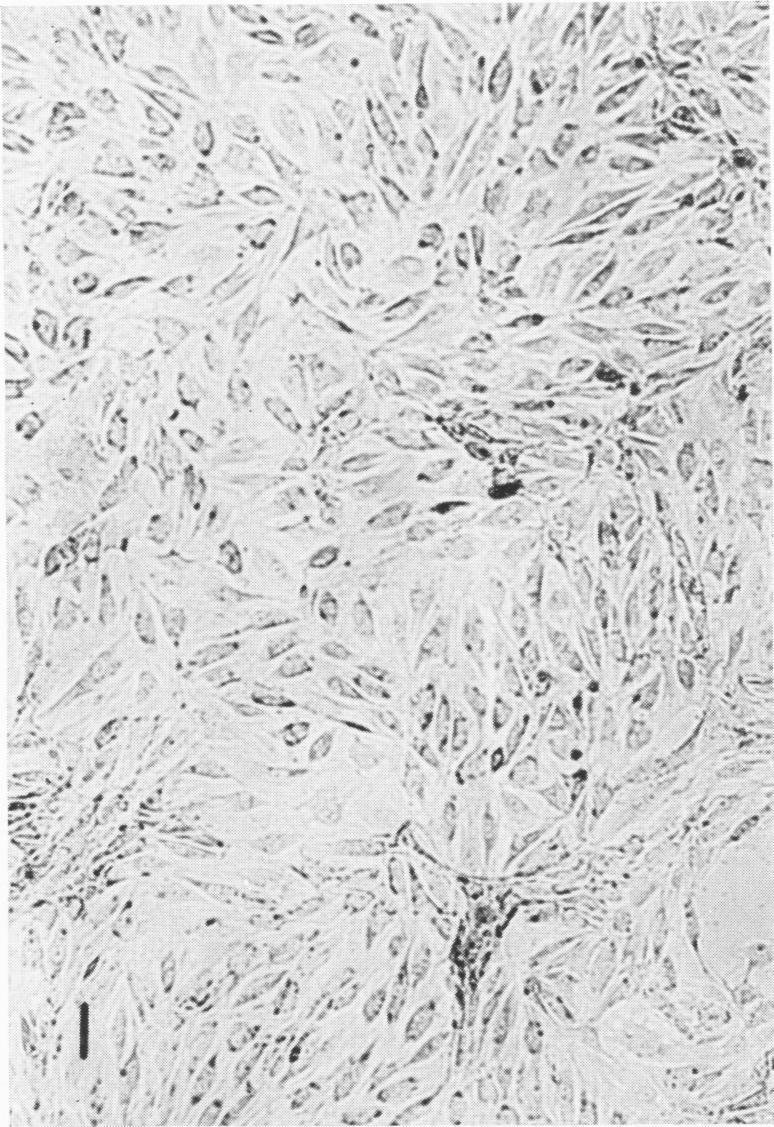

An agent which possesses the physical, chemical, cytopathic, histological, and electron microscopic attributes of a herpes group virus was isolated from an uninoculated batch of primary rabbit kidney cell cultures. Preliminary evidence indicates that antibodies against the agent are found in some sera of other "normal" New Zealand albino rabbits. In cell cultures, the virus grew best and almost exclusively in cells of rabbit origin. On the basis of these facts, the name herpesvirus cuniculi (HC) is suggested for the isolate. A batch of anti-herpesvirus bovis antiserum prepared in rabbits was found to be "contaminated" with unsuspected neutralizing antibodies against HC. Caution is mandatory when using rabbits, rabbit tissues, or rabbit sera for work with any herpes group virus unless precautions are taken to rule out unsuspected infection with or antibodies against HC. This agent may well represent a reisolation of virus III, a rabbit herpes virus, described by Rivers in 1923; the isolation of this virus has not been reported since 1940. It is important to reemphasize the existence of this agent in an animal which is commonly used for laboratory investigation of herpes group viruses.

从一批未接种的原代兔肾细胞培养物中分离出一种具有疱疹病毒群病毒的物理、化学、细胞病变、组织学和电子显微镜特征的病原体。初步证据表明,在其他“正常”新西兰白兔的一些血清中发现了针对该病原体的抗体。在细胞培养中,该病毒生长良好,几乎只在兔源细胞中生长。基于这些事实,建议将该分离株命名为兔疱疹病毒(HC)。发现一批在兔体内制备的抗牛疱疹病毒抗血清“污染”了针对HC的意外中和抗体。在使用兔、兔组织或兔血清进行任何疱疹病毒群病毒的研究时,必须谨慎,除非采取预防措施排除意外感染HC或针对HC的抗体。这种病原体很可能是1923年里弗斯描述的病毒III(一种兔疱疹病毒)的重新分离;自1940年以来尚未报道过这种病毒的分离情况。再次强调这种病原体在一种常用于疱疹病毒群病毒实验室研究的动物中的存在很重要。